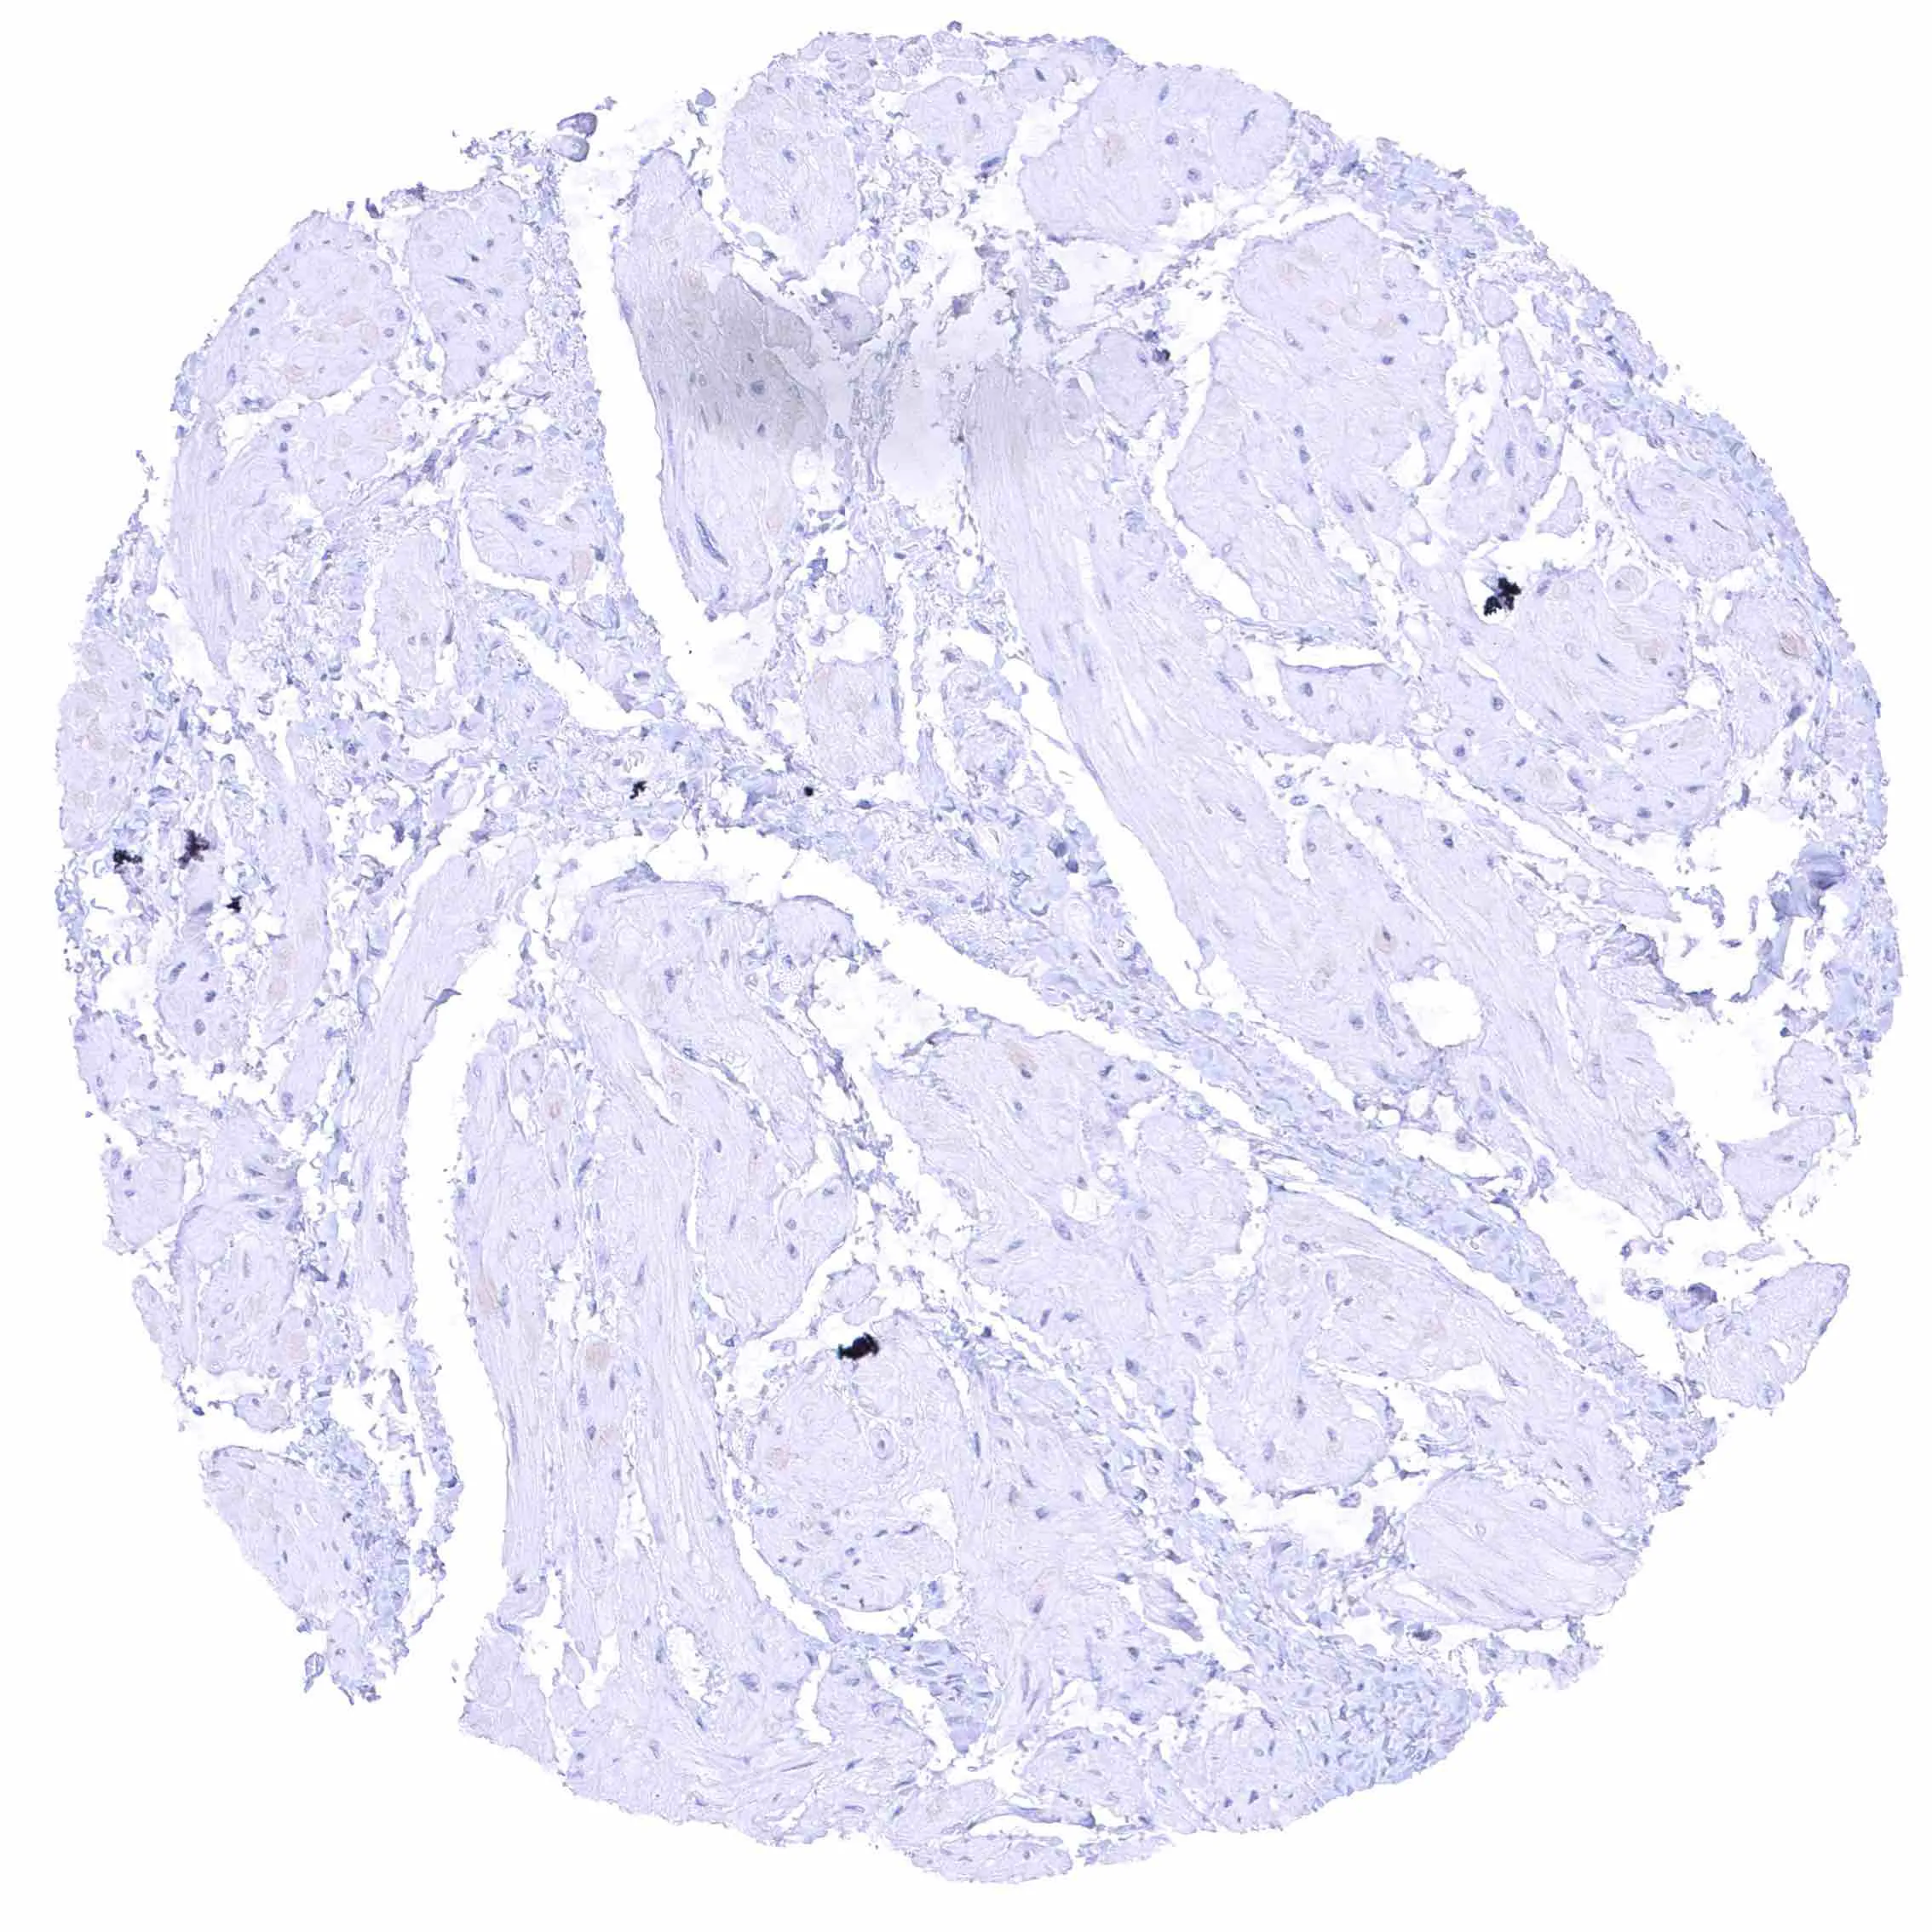

Urinary bladder, muscular wall